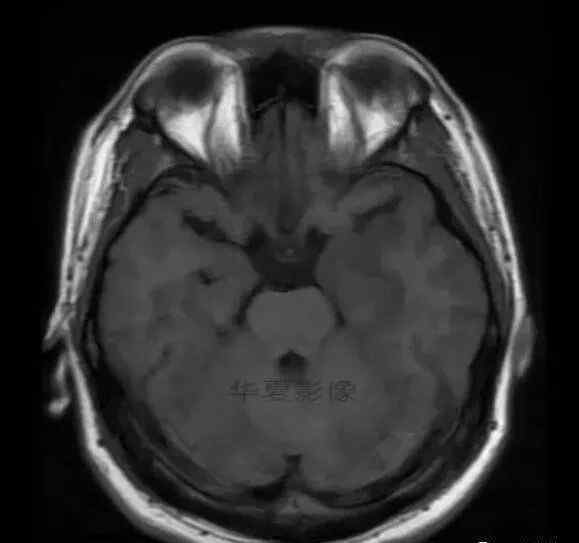

男,25岁,6天前意外感冒,现在发烧。他的体温超过39.0℃,他的呕吐物不是喷射状的。他的呕吐物是胃里的东西。

1.左侧颞叶、海马和岛叶T1WI信号低,T2WI信号高

2.病变没有明显的边界

3.占用效果不明显

4.豆状核不受影响